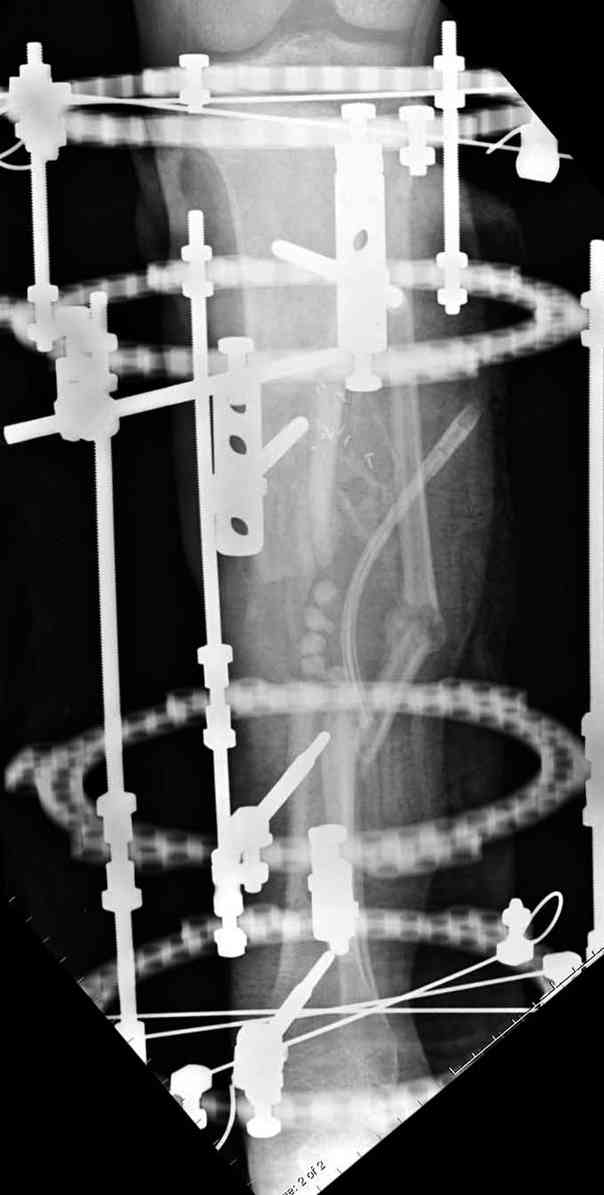

3,4 - через 4 недели наложен спице-стержневой аппарат, произведена остеотомия большеберцовой кости в верхней трети, раны зажили, проводилась дистракция в аппарате.